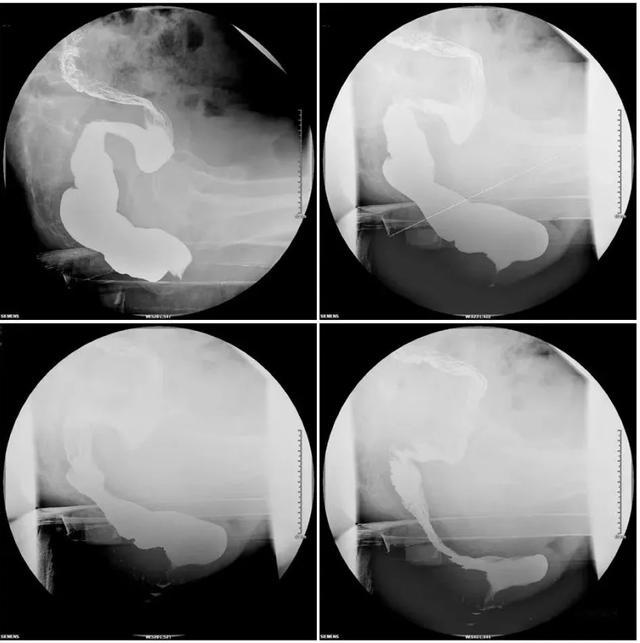

排粪造影检查是一种用于诊断排便功能障碍的影像学检查方法。检查时,会将适量的造影剂(通常是钡剂)注入直肠,然后让患者坐在特制的马桶上,在X线透视下动态观察排便过程中直肠、肛管等部位的形态和功能变化。

这种检查可以清晰地显示直肠黏膜脱垂、直肠套叠、会阴下降、盆底痉挛综合征等多种导致排便困难的异常情况,帮助医生发现病变位置、评估病情严重程度,为后续治疗提供重要依据。

排粪造影又称排便直肠造影,将钡剂灌入直肠后,让病人坐在特制的马桶上,当病人“排粪”时,将其肛管直肠部运动、静态相合。通过这项检查,医生可以了解患者是器质性病变或功能性异常,如肛门失禁、便秘等,从而制定相应的治疗方案。